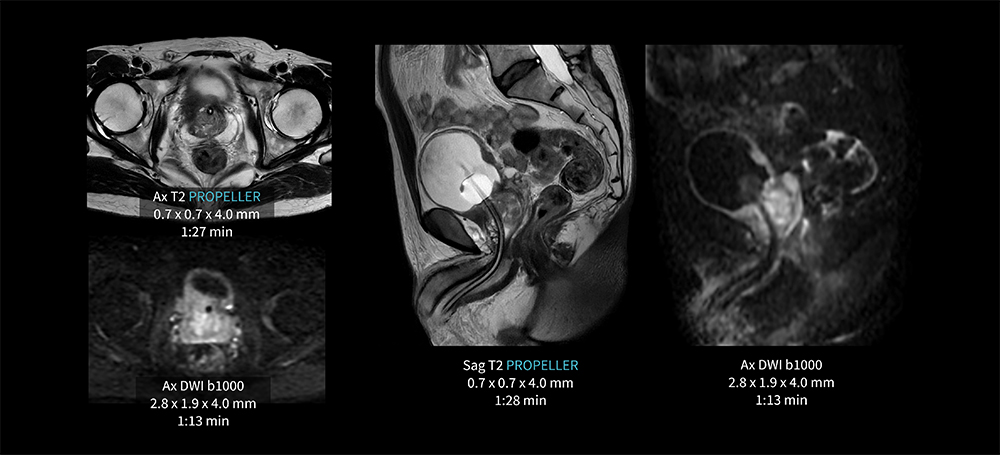

Case7 PROPELLER/膀胱癌

50代、男性。膀胱癌の前立腺浸潤疑い。膀胱右後壁の肥厚。

AIR Recon DL併用のPROPELLERにより膀胱の動きの抑制が可能となり、各シーケンス1分台の短時間撮像を実現している。

MR30_Kariyatoyota_09.jpg図7 PROPELLER を用いた膀胱検査